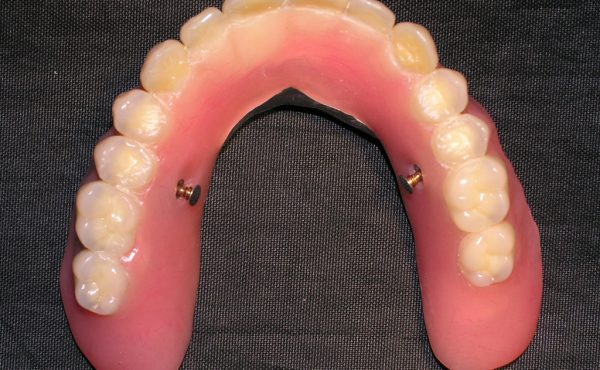

La siguiente paciente es una Señora. de 65 años de edad, la cual no tenía dientes en el maxilar y utilizaba una dentadura total convencional, la cual cubre el paladar totalmente. La paciente quería otra opción protésica ya que el paladar de la dentadura le ocasionaba nauseas además de que perdía el sabor de los alimentos.

Se le colocaron siete implantes para realizarle una dentadura sin paladar, la cual es más delgada y el paladar queda libre.

caso 5-2

Se unieron estos implantes por medio de dos barras de oro, para soportar la dentadura y darle mayor retención.

caso 5-3